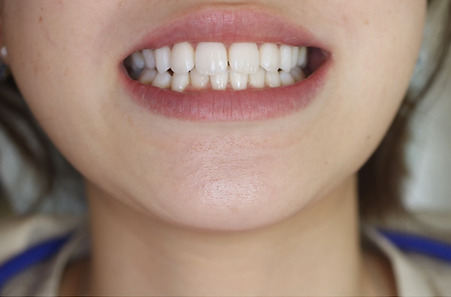

以下の写真はR4.9月に撮影した写真です。

2022年現在72歳の女性の方です。

治療が終了してから13年経過していますが、今も大丈夫です。